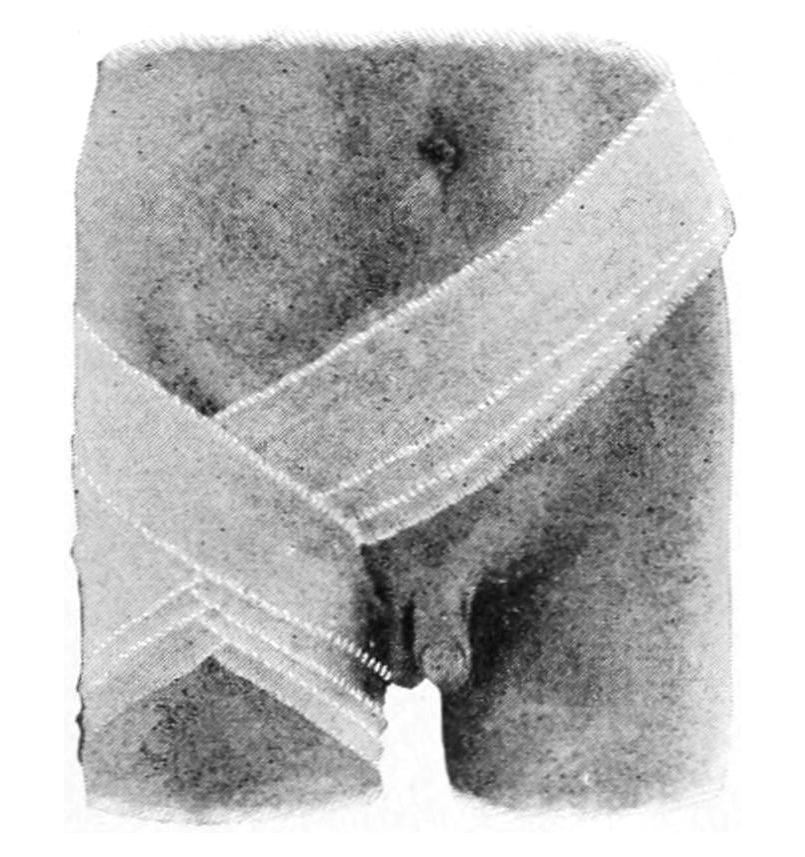

—When the effusion above referred to takes place into loose connective tissues the condition is spoken of technically as edema, while when it occurs into a previously existing cavity, such as that of a joint, it is known as an effusion. The amount of blood thus effused will be influenced by the anatomical and mechanical conditions existing about the part. It may be presumed, as a general rule, that when the extra vascular pressure equals the intravascular pressure little or no more fluid may escape. As a matter of fact, it is seldom that the former rises to the degree of the latter. Conversely, one method of treating such edemas and effusions is by some device which shall make the extravascular pressure exceed the intravascular, when the fluid is, as it were, forced back into the vessels, and is made to resume its proper place within the same. This is often done by taking advantage of elastic compression, as when a rubber bandage is applied about the part. In certain parts of the body it may be done by pressure brought about by some other device. Pressure may be used for two purposes:

A. To so increase extravascular pressure as to limit the possible amount of an effusion, as when it is put on early after an injury; or,

B. When it is used as a later resort for the purpose of reducing swelling which has already occurred.

Toward the end first mentioned—namely, the limitation of hyperemia—we may adopt local and general measures. Local measures include graduated pressure, providing this is not intolerable to the patient, so equalized that outside of the vessels it shall equal that inside. This may be done by careful bandaging, extreme care being taken that the pressure be applied from the very extremity of the limb; otherwise, passive exudation might be augmented and gangrene be precipitated. Elevation of a limb will often accomplish the same purpose. Cold, which is in effect an astringent and which tends to contract bloodvessels, is another measure in the same direction, and if applied early will do much to limit the degree of the attack. This may be applied as dry or moist cold, and should be gradually mitigated as the congestion subsides. It acts through the vasomotor system, and is a measure to be resorted to with caution. An efficient way of applying dry cold can be extemporized by a few yards of rubber tubing, held in place by wire or sewed in place to a piece of cloth, through which a stream of cold water is permitted to pass.